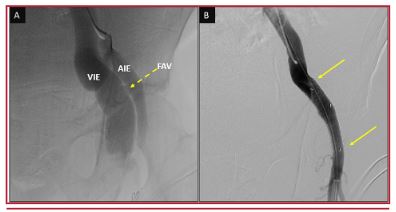

Insuficiencia cardíaca por fístula arteriovenosa ilíaca externa post-ablación con láser de la vena safena